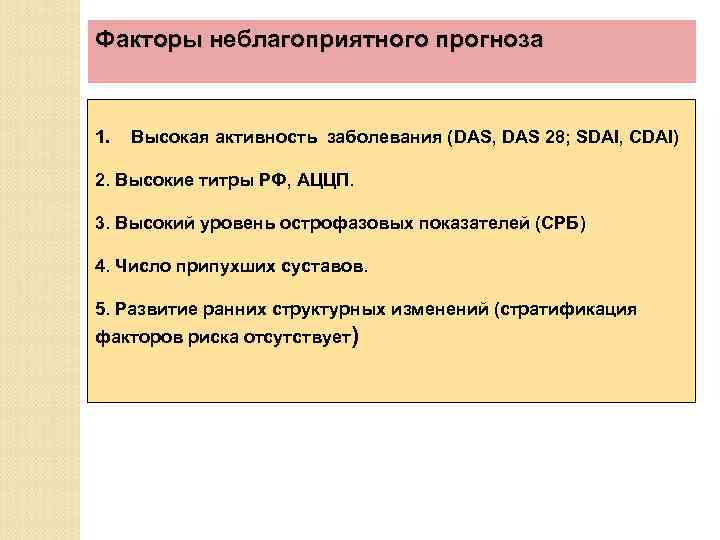

Факторы неблагоприятного прогноза 1. Высокая активность заболевания (DAS, DAS 28; SDAI, CDAI) 2. Высокие титры РФ, АЦЦП. 3. Высокий уровень острофазовых показателей (СРБ) 4. Число припухших суставов. 5. Развитие ранних структурных изменений (стратификация факторов риска отсутствует)

Факторы неблагоприятного прогноза 1. Высокая активность заболевания (DAS, DAS 28; SDAI, CDAI) 2. Высокие титры РФ, АЦЦП. 3. Высокий уровень острофазовых показателей (СРБ) 4. Число припухших суставов. 5. Развитие ранних структурных изменений (стратификация факторов риска отсутствует)